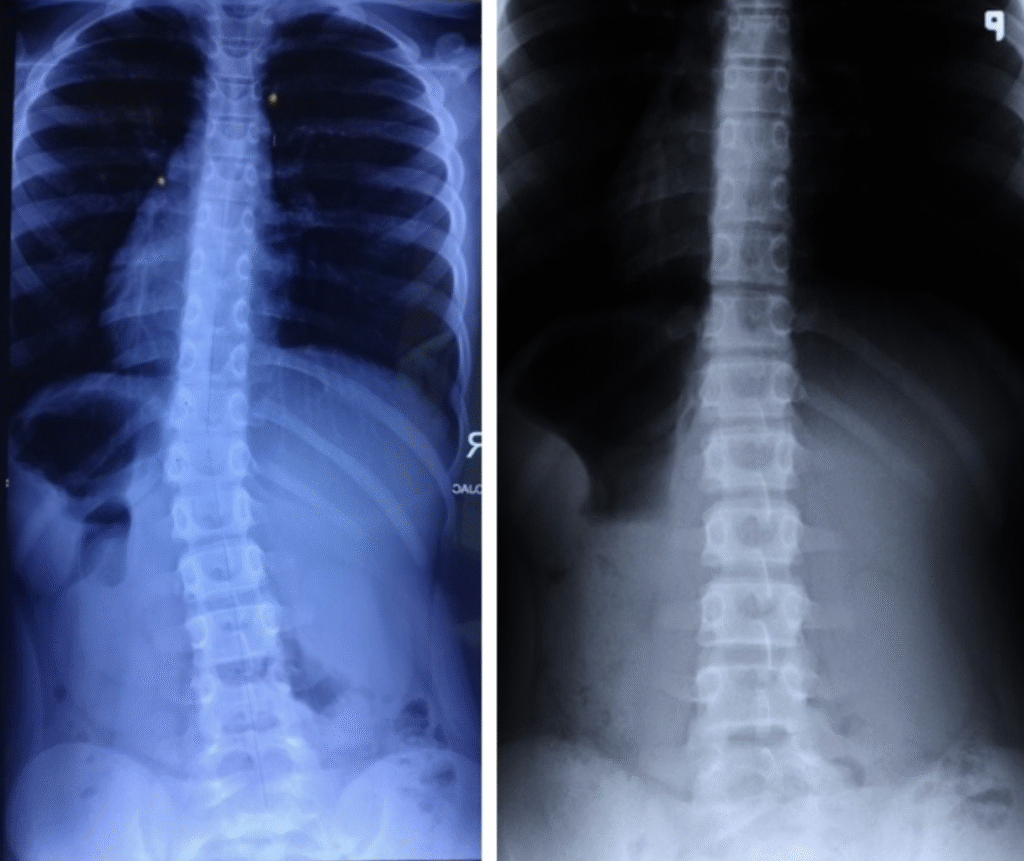

Magda – 11 lat

Terapia prowadzona w okresie 13.01 – 06.04.2016 (16 zabiegów) Częstotliwość zajęć – 10 zabiegów 2 x tydz., 6 zabiegów 1 x tydz.

Kacper – 9 lat

Terapia prowadzona w okresie 01.09 – 03.11.2016 (22 zabiegi) Częstotliwość zajęć – 2 x tydz.